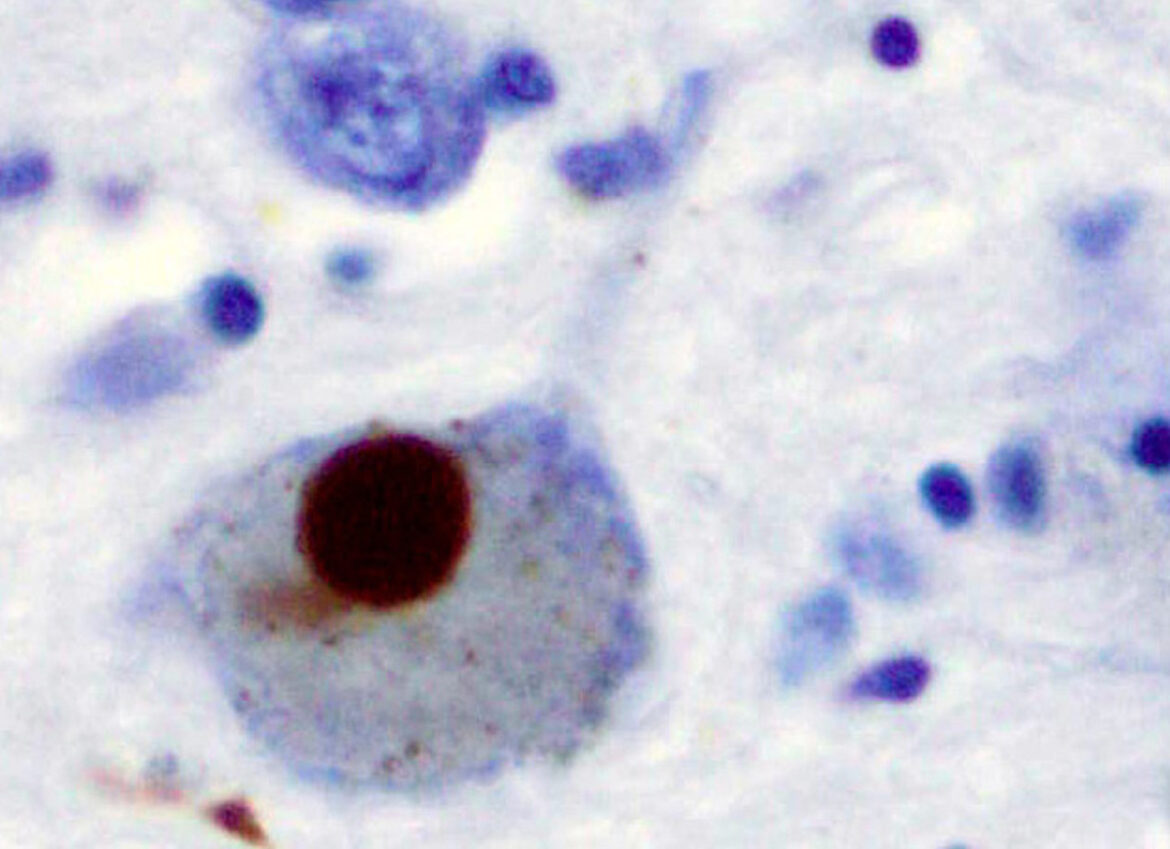

Однако болезнь Альцгеймера — не единственный пример того, как нарушение работы белков приводит к разрушению нервной системы. Схожие процессы лежат в основе и других нейродегенеративных заболеваний. В частности, при болезни Паркинсона ключевую роль играет другой белок — α-синуклеин. В норме он участвует в передаче сигналов между нейронами, но при болезни также начинает сворачиваться неправильно и образовывать скопления внутри клеток мозга. Эти скопления, известные как тельца Леви, повреждают нейроны и постепенно нарушают работу двигательных центров мозга. В итоге мозг, когда-то пластичный и живой, оказывается заблокирован собственными биохимическими обломками.

Прионный белок. Изображение на обложке: Прионный белок, иллюстрация: PoopAcidMaker, CC BY-SA 4.0, via Wikimedia Commons